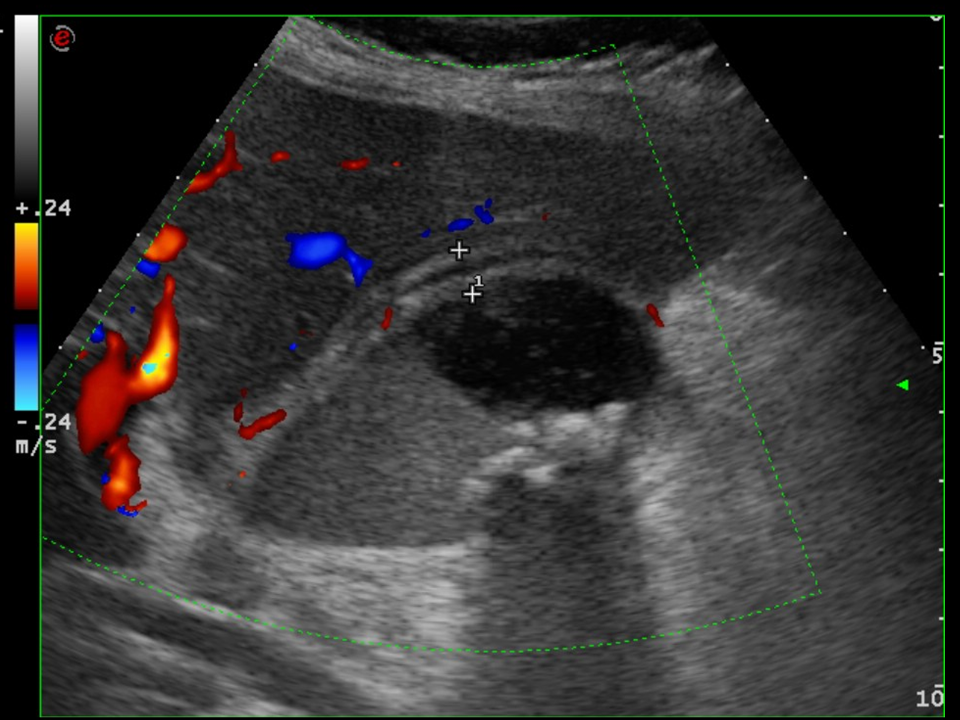

• Sometimes, the presence of a right subcostal radiopaque stone on a plain abdominal radiograph can confirm the suspicion of cholelithiasis, cholecystitis. The method of choice however, is ultrasonography. US examination can depict stones located either in the gall bladder or in the biliary tract. They are shown as hyperreflective structures with acoustic shadowing. As a sing of inflammation the bladder wall thickens, becomes multilayered and edematous. Doppler examination can reveal the consequent hypervascularization of the inflammation. When US is unable to examine the extrahepatic biliary ducts, CT will not provide additional information because the choleliths might not be radiopaque. In these cases MRCP might be indicated.

17. Typical right subcostal colic pain. Ultrasound examination. On the right is a typical picture of a cholelith with acoustic shadowing. The left image shows cholecystitis with multilayered, edematous and hypervascularized gall bladder wall. Note the intraluminal dense sludge and the presence of multiple, small gallstones.